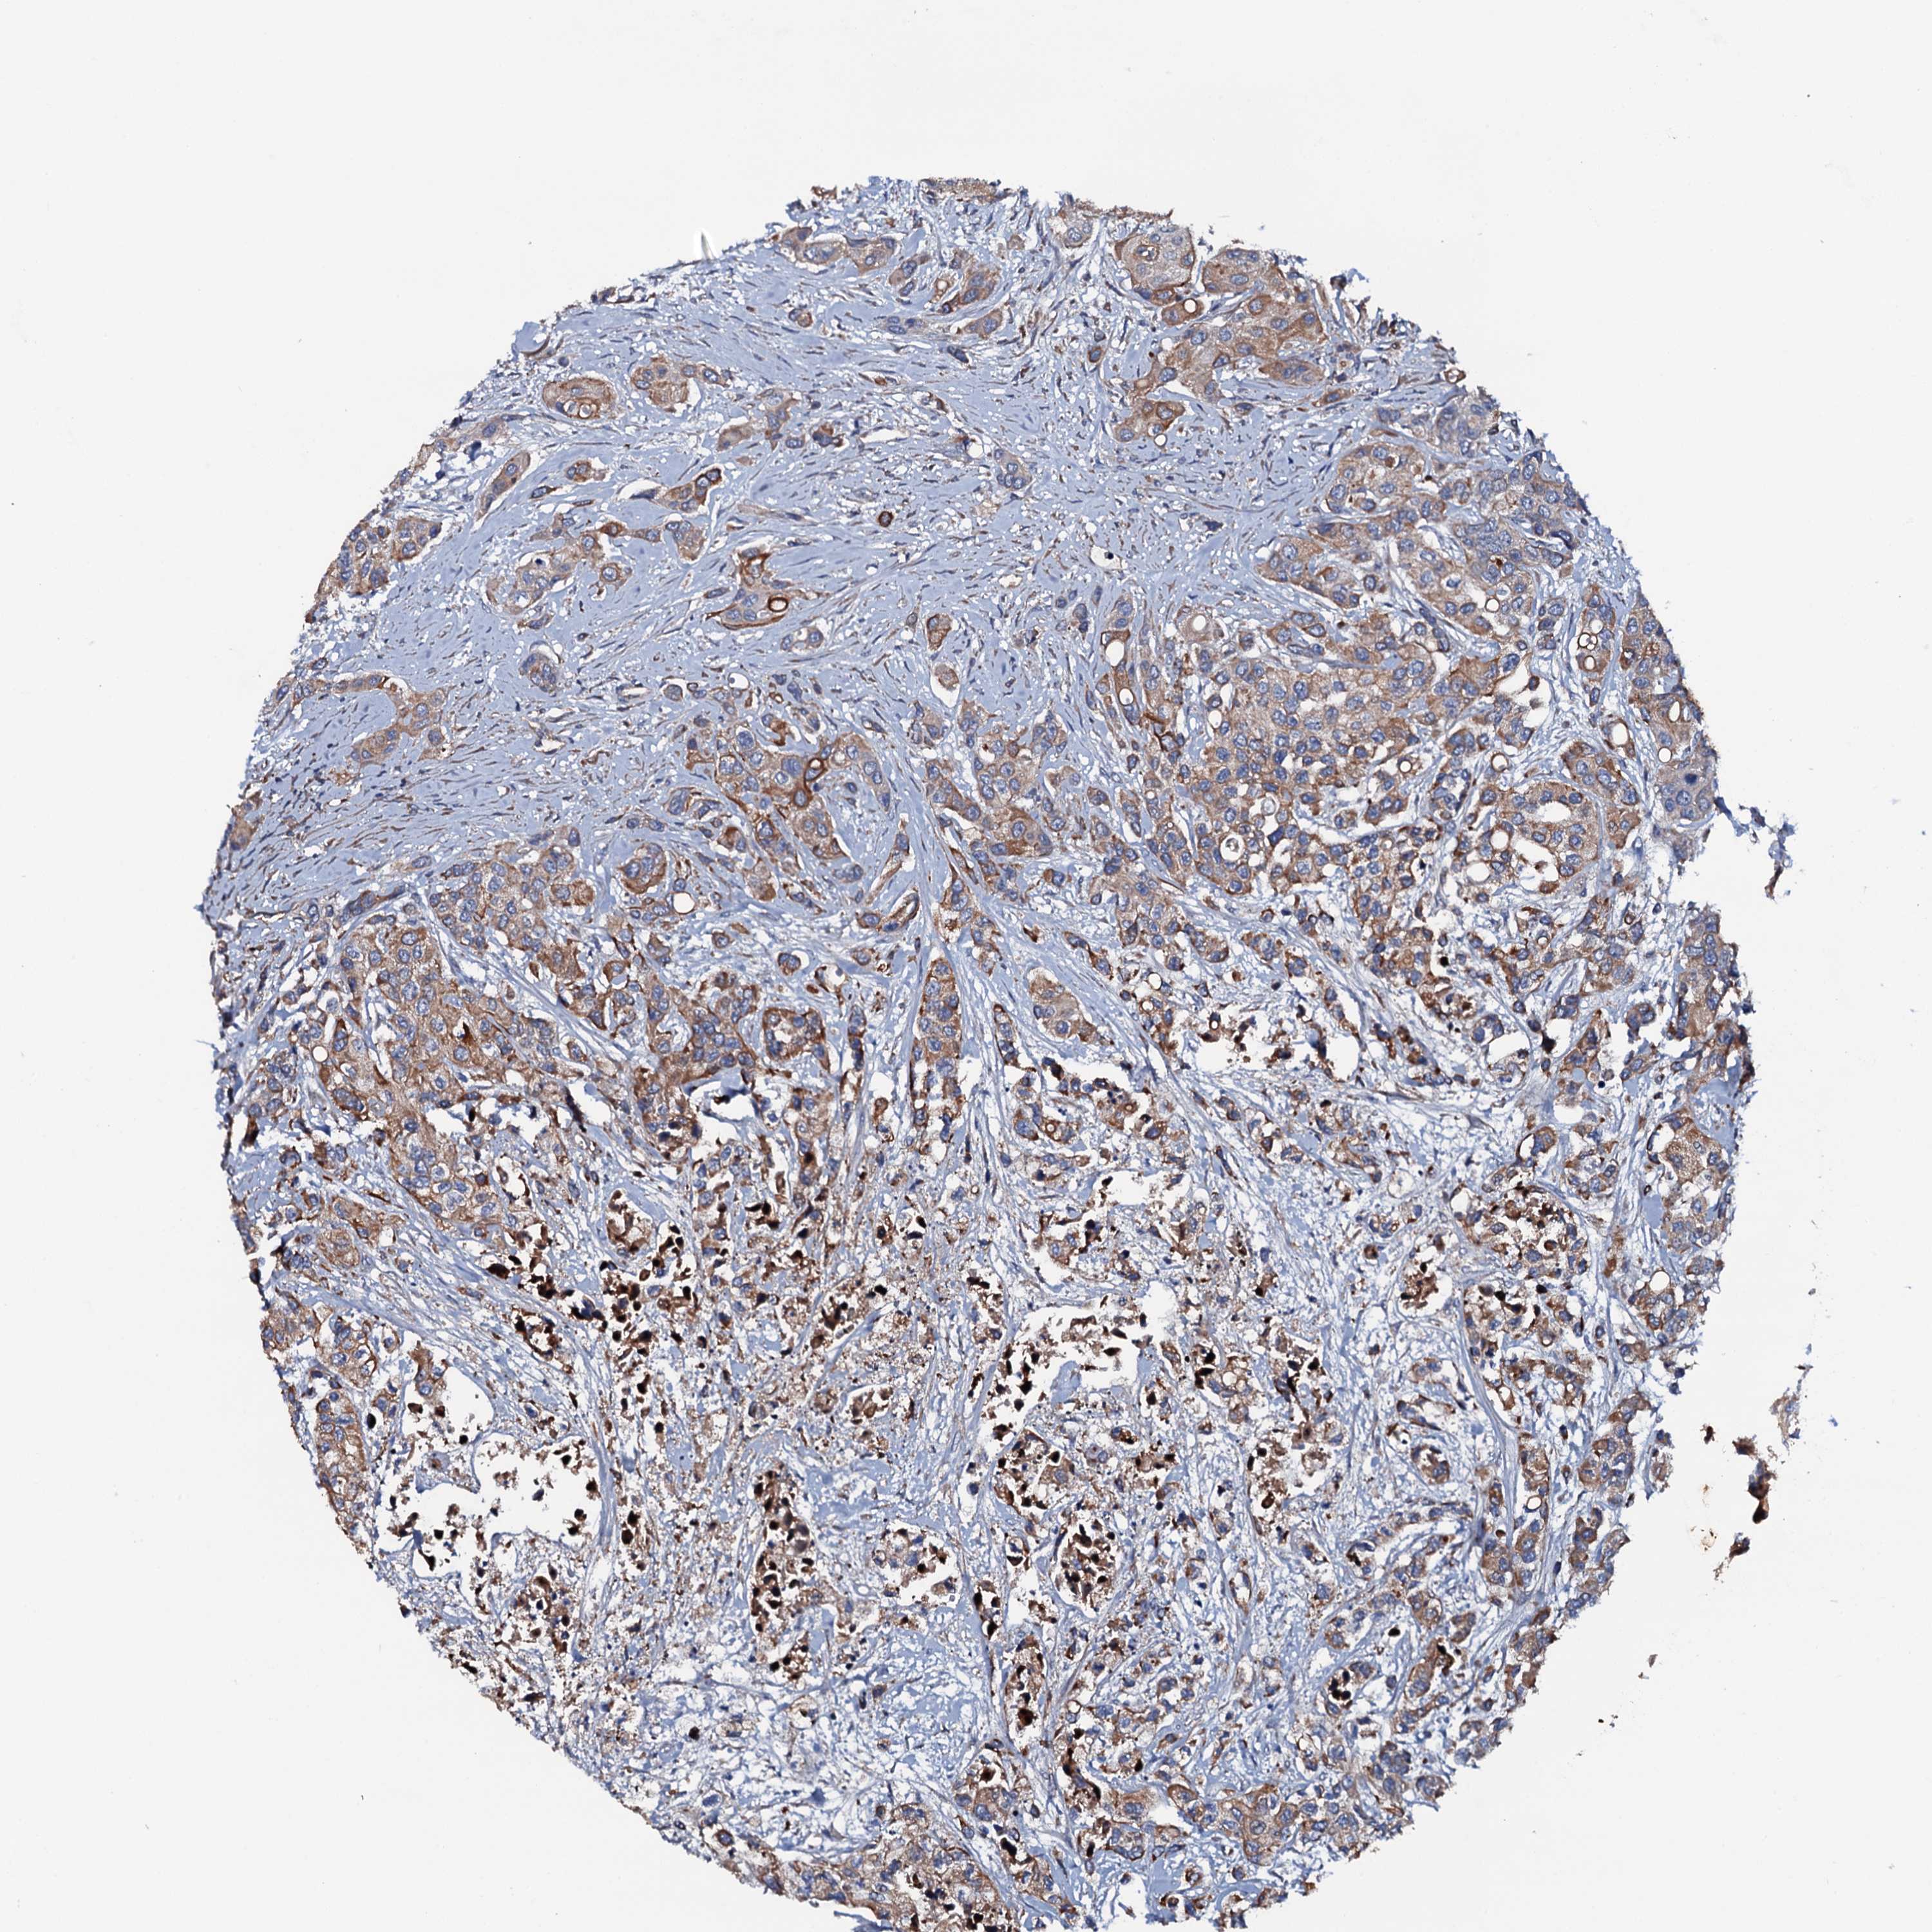

UROTHELIAL CANCER - Protein expressioni

A mouse-over function shows sample information and annotation data. Click on an image to view it in a full screen mode. Samples can be filtered based on level of antibody staining by selecting one or several of the following categories: high, medium, low and not detected. The assay and annotation is described here.

Note that samples used for immunohistochemistry by the Human Protein Atlas do not correspond to samples in the TCGA dataset.

Antibody stainingi

Antibody staining in the annotated cell types in the current human tissue is reported as not detected, low, medium, or high, based on conventional immunohistochemistry profiling in selected tissues. This score is based on the combination of the staining intensity and fraction of stained cells.

Each image is clickable and will lead to virtual microscopy that enables deeper exploration of all samples and also displays staining intensity scores, fraction scores and subcellular localization as well as patient and tissue information for each sample.

Antibody HPA020873

Antibody HPA040413

Urothelial carcinoma, High grade

Urothelial carcinoma, Low grade

Urothelial carcinoma, NOS